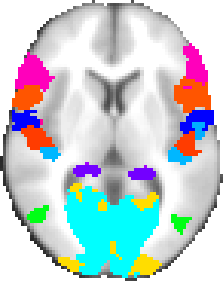

Harvard-Oxford cortical and subcortical structural atlases

Probabilistic atlases covering 48 cortical and 21 subcortical structural areas, derived from structural data and segmentations kindly provided by the Harvard Center for Morphometric Analysis.

Probabilistic atlases covering 48 cortical and 21 subcortical structural areas, derived from structural data and segmentations kindly provided by the Harvard Center for Morphometric Analysis.

T1-weighted images of 21 healthy male and 16 healthy female subjects (ages 18-50) were individually segmented by the CMA using semi-automated tools developed in-house. The T1-weighted images were affine-registered to MNI152 space using FLIRT (FSL), and the transforms then applied to the individual labels. Finally, these were combined across subjects to form population probability maps for each label.

We are very grateful to the following for providing the segmentations used to create these atlases: David Kennedy and Christian Haselgrove, Centre for Morphometric Analysis, Harvard; Bruce Fischl, the Martinos Center for Biomedical Imaging, MGH (NIH grants P41-RR14075, R01 RR16594-01A1, R01 NS052585-01); Janis Breeze and Jean Frazier from the Child and Adolescent Neuropsychiatric Research Program, Cambridge Health Alliance (NIH grants K08 MH01573, K01 MH01798); Larry Seidman and Jill Goldstein from the Department of Psychiatry of Harvard Medical School.